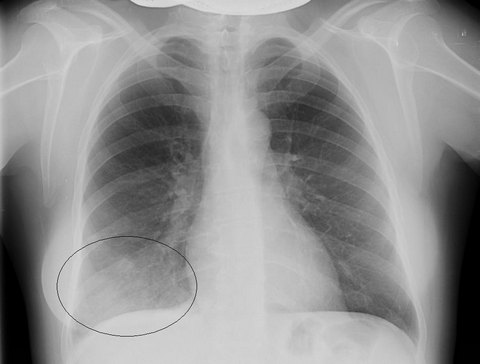

- рентгенография. При правосторонней среднедолевой пневмонии на рентгеновском снимке визуализируется затемнение участка в средней доле правого легкого, наличие одиночного или множественных очагов;

Рентгенограмма лёгких при сегментарной пневмонии